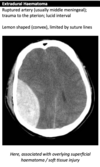

Extradural

Extradural on CT head